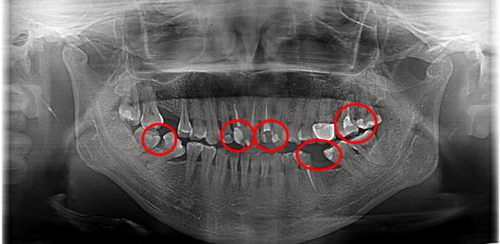

对于牙列拥挤不齐的一些患者来说,如果牙缝清洁工作不到位,邻面龋就很容易发生。

上图一位患者的牙片,很明显因为牙齿拥挤不齐,其中仍有食物嵌塞残留,也就是在牙齿邻接面。这种如果长期嵌塞无法清洁,就会导致牙龈和牙槽骨的炎症、退缩。